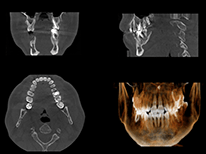

CTスキャンを導入しているか

インプラント治療では、CTスキャンを導入している医院を選ぶことが重要です。

CTスキャンは、顎の骨の厚みや神経・血管の位置を3D画像で正確に把握できるため、安全で精密な治療計画を立てるのに欠かせません。レントゲンのみの診断では、骨の状態を正確に判断できないこともあるため、CTスキャンを用いた診断を行う医院を選ぶと安心です。

カウンセリング時に、CT撮影の有無やその結果に基づいた説明をしてくれるかを確認しましょう。